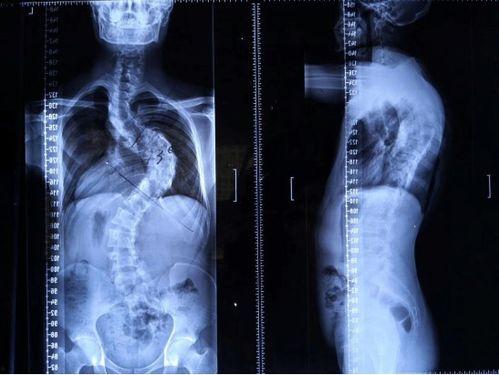

脊柱矫正,顾名思义,就是通过各种方法来调整脊柱的形态,使其恢复到正常状态。这个过程可能涉及到物理治疗、按摩、针灸、手术等多种手段。那么,成人还能矫正脊柱吗?答案是肯定的!

脊柱矫正的原理其实很简单,就是通过外力来改变脊柱的受力点,从而逐步调整脊柱的形态。这个过程需要耐心和毅力,因为脊柱矫正并非一蹴而就的事情。

脊柱矫正的效果因人而异,但一般来说,经过一段时间的治疗,大部分患者的脊柱都会得到明显改善。具体效果如下: